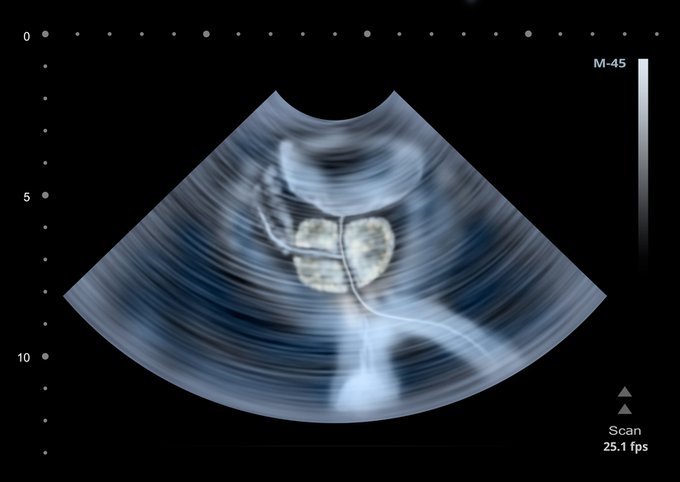

¿Cuáles son los factores de riesgo del cáncer de próstata? Aquí lo que debes saber ow.ly/Omuz50xbKey